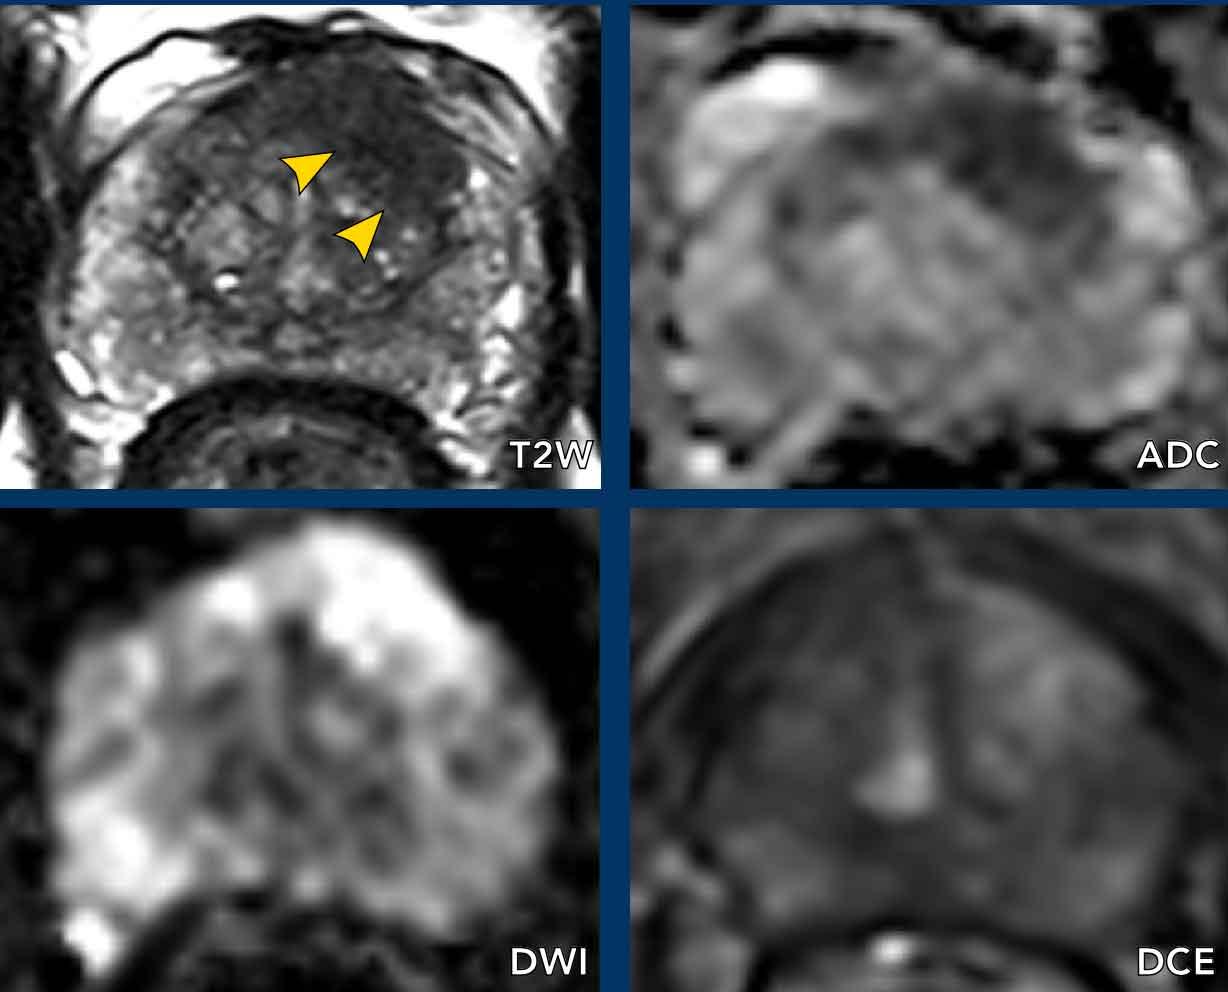

Các phát hiện bao gồm:

- Một tổn thương phân loại đánh giá PI-RADS 4 nằm ở vùng ngoại vi bên trái của phần giữa tuyến tiền liệt.

Giảm tín hiệu rõ rệt khu trú trên ADC (mũi tên vàng) (điểm 4), tương ứng với vùng giảm tín hiệu trên chuỗi xung T2W (điểm 4).

Điểm Gleason của tổn thương này là 3+4.

- Một tổn thương phân loại đánh giá PI-RADS 3 nằm ở vùng ngoại vi bên phải, với giảm tín hiệu khu trú nhẹ trên ADC (mũi tên xanh lá) và đồng tín hiệu trên DWI (điểm 3).

Không thực hiện DCE và không thể phân biệt thêm được.

Sinh thiết không cho thấy bất kỳ dấu hiệu ác tính nào.